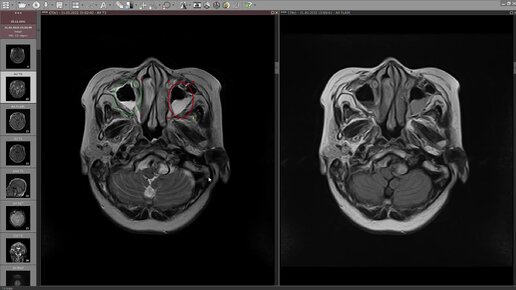

МРТ головного мозга. Разбор клинического случая №1